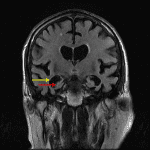

- Symmetric volume loss involving both temporal lobes and hippocampi with ex vacuo enlargement of the temporal horns of both lateral ventricles, which is out of proportion to the degree of generalized cerebral and cerebellar volume loss

Advanced bilateral temporal and hippocampal volume loss out of proportion to the over degree of cerebral atrophy, which can be seen with Alzheimer disease.

- Mesial temporal lobes including the entorhinal cortex and hippocampus (especially CA-1) – look for disproportionate ex vacuo enlargement of the temporal horns